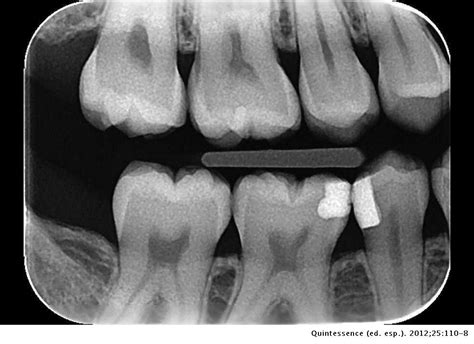

- Radiografías de aleta de mordida: Ideales para detectar caries interproximales.

Si no se realiza un control periódico, las caries incipientes (iniciales) van avanzando y pueden llegar a afectar la pulpa dental (nervio). En obturaciones antiguas (empastes/reconstrucciones) controlaremos que los márgenes de las restauraciones estén correctos, ya que en el material artificial no se producirán caries, pero en el tejido dental de alrededor sí podrían aparecer filtraciones. En la imagen que señala la flecha vemos una imagen radiolúcida (oscura) que indica la falta de material dental, la presencia de una zona “hueca”. Caries.